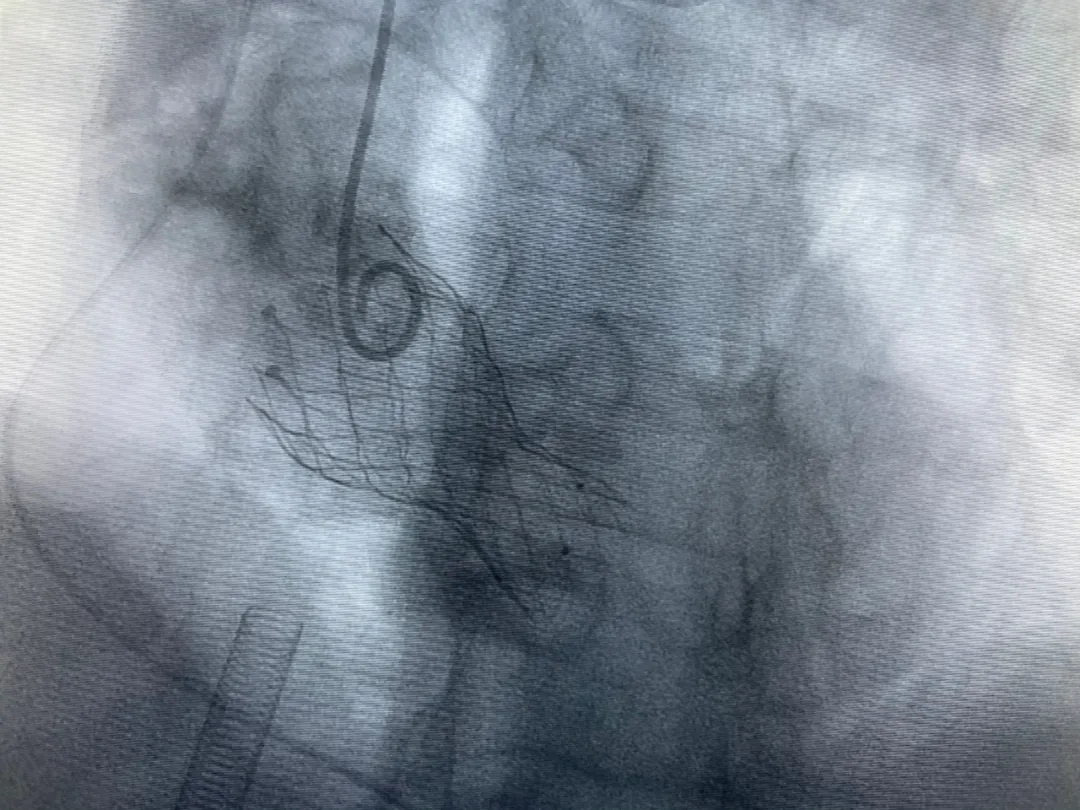

結(jié)合老人病情特點(diǎn):年齡高、室壁厚、左室腔小、瓣膜鈣化嚴(yán)重,術(shù)中球囊擴(kuò)張和瓣膜釋放過程有循環(huán)崩潰可能;為降低此種風(fēng)險(xiǎn)、最大程度提高手術(shù)成功率,張金洲副院長在術(shù)前組織了由楊金保博士帶領(lǐng)的TAVR團(tuán)隊(duì)多次反復(fù)溝通、討論,制定了各種應(yīng)急處理方案。最終經(jīng)過TAVR團(tuán)隊(duì)的默契配合,手術(shù)歷時(shí)2小時(shí),用20#球囊預(yù)擴(kuò)張后順利植入23#主動脈瓣生物瓣膜,再次后擴(kuò)后主動脈根部造影顯示:人工主動脈瓣生物瓣位置良好,瓣葉開閉正常;冠脈顯影良好。經(jīng)食道超聲顯示:主動脈瓣葉活動度良好,主動脈跨瓣壓差約35mmHg,未見瓣周漏及明顯返流。出手術(shù)室前老人便已蘇醒,自訴憋悶癥狀完全消失。